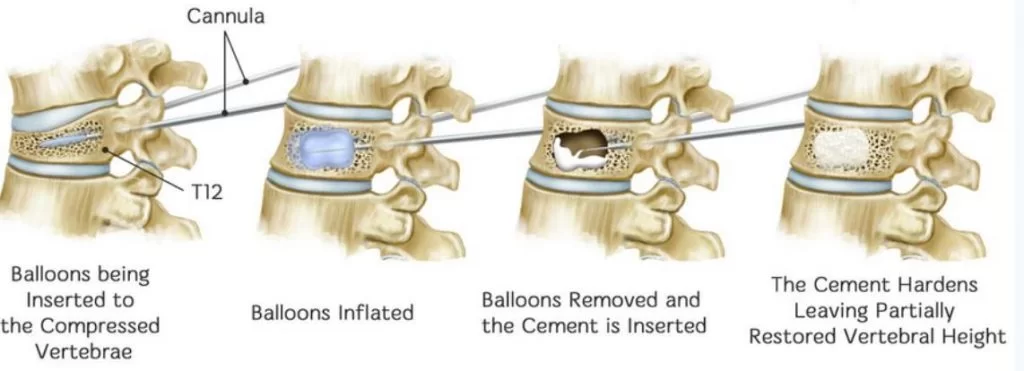

Με τη σπονδυλοπλαστική, εγχύεται ένα μίγμα οστικού «τσιμέντου» στον σπόνδυλο, προκειμένω να τον ισχυροποιήσει. Η διαφορά με την κυφοπλαστική είναι ότι στην κυφοπλαστική χρησιμοποιείται πρίν την έγχυση του τσιμέντου ένα μπαλόνι, το οποίο φουσκώνει μέσα στον σπόνδυλο, προκειμένω να αποκατασταθεί το ύψος και το σχήμα του σπονδύλου (Εικόνα 1 και 2).